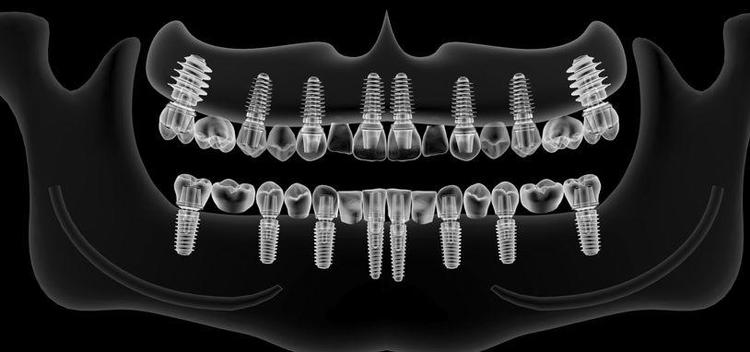

诚和植牙優勢

1. 最新3D高科技醫療設備

本院设备最新植牙專用3D (CBCT) 体影像設備,可決定最佳的植入位置 角度,大幅度提高植牙的安全性, 成 率, 與準確度。

2. 植體材料優勢

本診所採用的是美國頂級FDA標準的植牙系統, 卓越的初期穩定性, 親骨性強, 癒合最快。

3. 微創植牙技術

疼痛程度低,傷口小且快速的植牙技術。

4. NYU 大學植牙醫師為您診治

本院植牙專師陳賜恆醫師具多張植牙證照與專利 ,包括紐約大學植牙部門的Implant Fellowship,能讓您安心與放心。 經驗豐富, 超過數千個成功案例; 接近100%成功率。

全口植牙的優點包含了:

1. 假牙穩定性高,不易鬆脫。

2. 支撐效果好,不易造成牙床破皮。

3. 咀嚼功能佳,一般稍硬食物均可化解。

4. 假牙體積減小,降低口腔不適感。

5. 重建後使用滿意度高。

6.当天种,当天用! 多颗人工牙根植入后,可以直接当天在上面安装固定假牙, 且不会影响种植牙的使用寿命。

真实病例